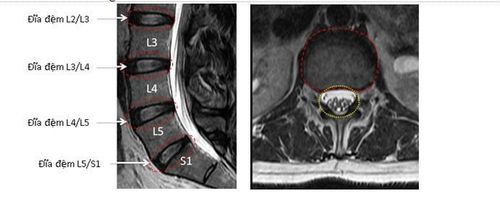

Hình MRI cột sống thắt lưng cắt dọc (bên trái) và cắt ngang (giữa): Thoát vị đĩa đệm L4/L5 (mũi tên đỏ), chèn ép nặng rễ thần kinh tọa L5 bên phải. Mũi tên xanh chỉ rễ L5 bị chèn ép đẩy lệch ra sau. Hình bên phải là sơ đồ đường đi rễ thần kinh tọa (bệnh nhân đau thần kinh tọa phải – dây thần kinh màu đỏ).